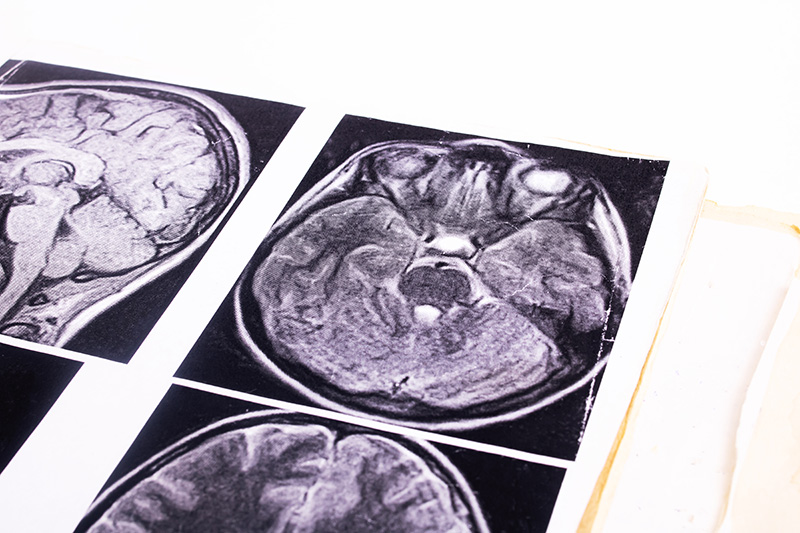

Для подтверждения диагноза медуллобластомы используются различные методы, которые помогают точно определить наличие и характер опухоли.

Диагностика медуллобластомы требует комплексного подхода и тесного взаимодействия между неврологами, нейрохирургами и онкологами. Это обеспечивает точное выявление заболевания и разработку эффективного плана терапии.